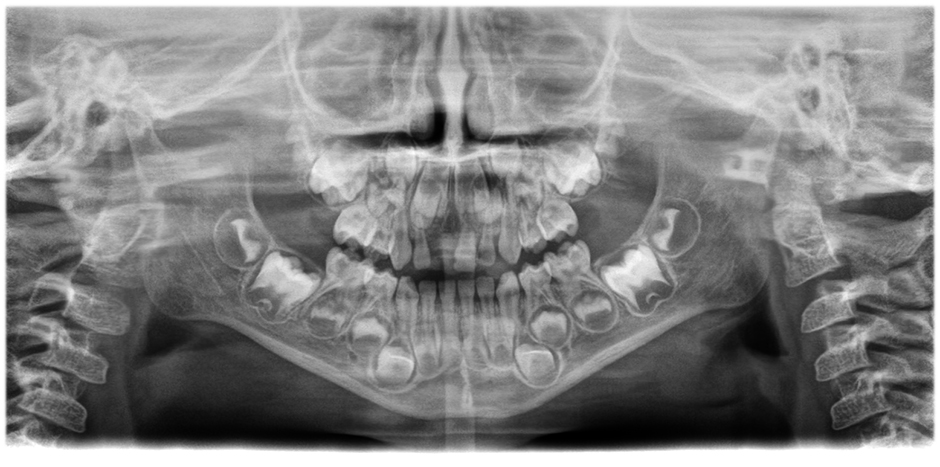

• Panoramiche incredibilmente chiare e definite

grazie ad un sistema di autofocus a 21 strati integrato nella funzione automatica di correzione della posizione del paziente. Scorri le immagini per vedere la differenza (panoramica di sinistra senza, panoramica di destra con autofocus e correzione della posizione del paziente)